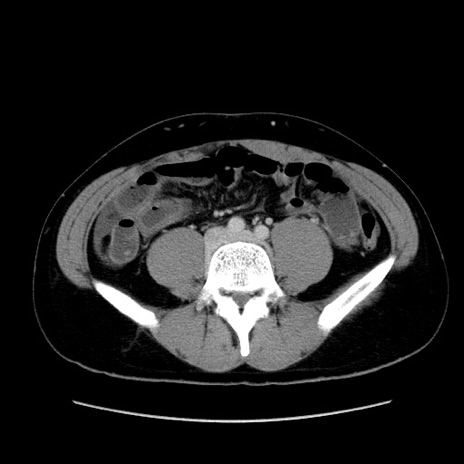

症例36(横断像)

【症例】20歳代 男性

【主訴】心窩部痛

【現病歴】今朝より上腹部痛あり。一旦軽快していたが再度出現したため救急要請。昨日夕に白身の魚を含む刺身を食べた。

【身体所見】BP 136/89mmHg、HR 74/min、BT 37.0℃、腹部:膨満、軟、心窩部に圧痛あり。反跳痛なし、筋性防御なし、腸雑音やや亢進あり。

【データ】WBC 17700、CRP 0.48